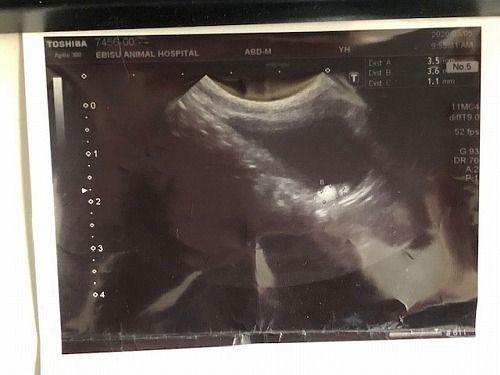

3週間後

そして...おととい再々度レントゲンを撮ったら

ガン巣が見えなくなっていた のだそうです